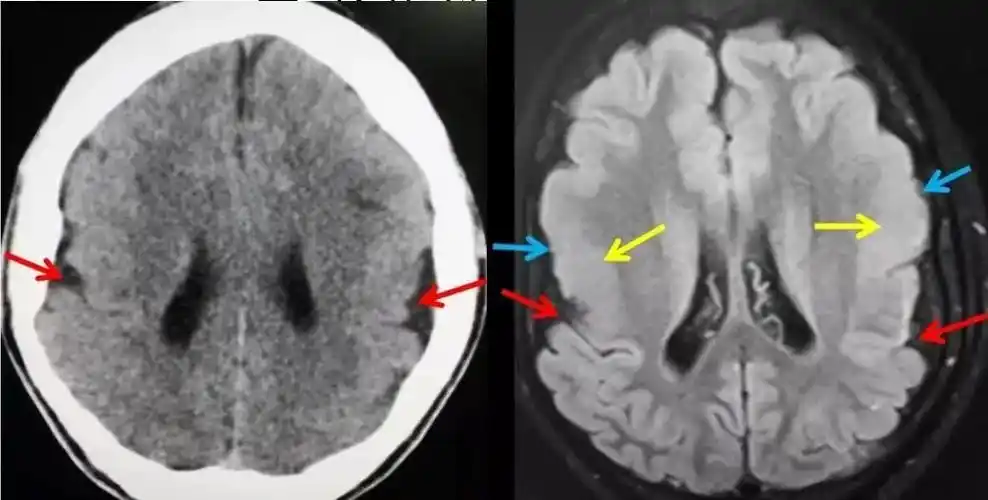

巨脑回畸形西安高尚医学影像病例

高尚病例:巨脑回畸形

行过程中受阻,导致脑组织不同程度的发育畸形,包括无脑回-巨脑回畸形